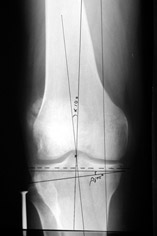

Большая просьба прокомментировать прилагавшиеся снимки. Видно, что сделано что-то красивое, но не совсем понятно, по какому поводу, как рассчитывалась коррекция, и что именно сделано.

Поводом для проведения всех корригирующих остеотомий у исследуемых пациентов служил гонартроз 1-3 стадии, косметическая коррекция в большинстве случаев являлась вторичной.

Хотя любого больного она не в меньшей степени интересовала. При всех видах остеотомий обязательным требованием являлась восстановление баланса пассивных и динамических сил путем восстановления оси конечности, стабильности связочного аппарата и контроля над мышечной активностью при осевой нагрузке. Как правило, учитывалась сохранность гиалинового хряща на компенсирующем нагрузку мыщелке бедра или большеберцовой кости. Предоперационное планирование осуществляли с поднагрузочных рентгенограмм обоих конечностей.

Дополнительными методами диагностики являлось измерение внутрикостного давления в зоне гипернагрузки и радионуклидные исследования нуклидами технеция. Применялись различные варианты остеотомий на различных сегментах. Для коррекции варусной-торсионной деформации:

высокие плюс, минус остеотомии большеберцовой кости,косая остеотомия малоберцовой. Для коррекции вальгусной деформации применялась плюс, минус надмыщелковая остеотомия бедренной кости. Фиксацию при высокой подмыщелковой остеотомии производили уникальной клинковой пластиной и тяговыми кортикальными винтами. Угол коррекции выставлялся

специальным угломером и направителем.

Поделитесь, пожалуйста, опытом, как Вам удается выполнять такие качественные рентгеновские снимки всей ноги полностью? На трех кассетах одновременно? Стыки кассет обычно <крадут> 1-2 см изображения. На снимке Вашего пациента <украденных> участков нет!

Качественные под нагрузочные рентгеновские снимки, получаются благодаря современному рентгеновскому оборудованию фирмы SIEMENS, (подробности могу уточнить у рентгенологов), а качественно стыковать (прозрачный скотч) научились с годами, но это для публикаций, для работы достаточно скрепить степлером по анатомическим осям с учетом толщины диафизов и грамотно расчертить. Пособие с удовольствием отправлю.